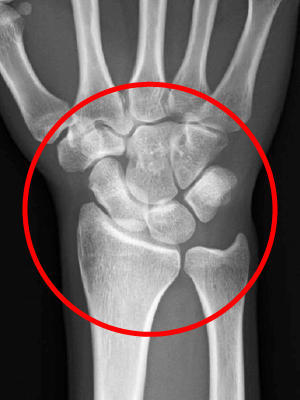

症例2

163歳の女性は、滑膜炎が進行し、関節の腫れや骨の変形が生じ、手の甲の腱が断裂してしまい、薬指や小指をピンと伸ばせない状態になりました。

2手術をして、滑膜の切除と腱の移行を行ったところ、手がきれいに伸びるようになりました。